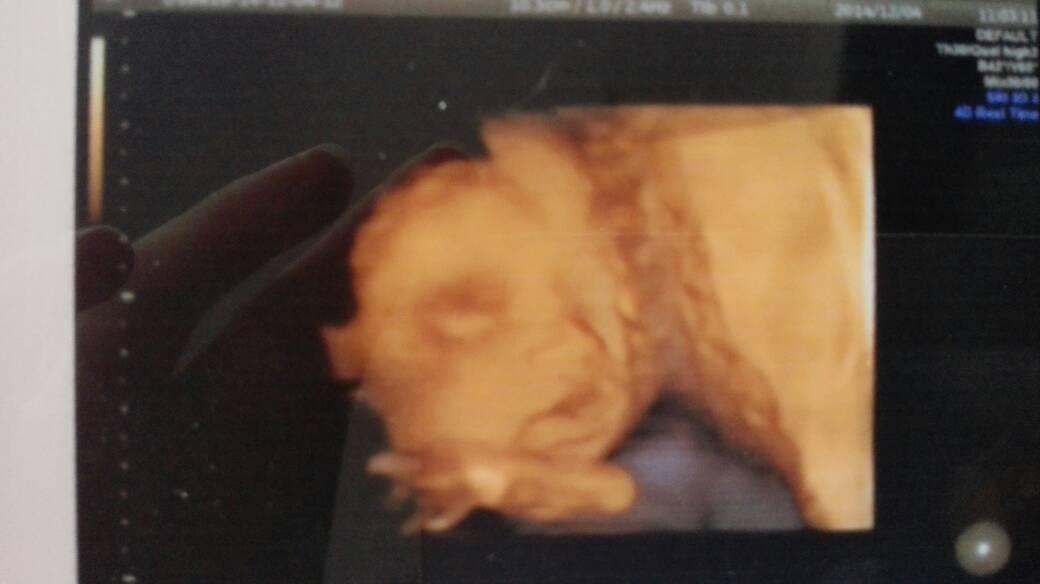

有没有已经做了四维彩超的亲啊?今天和老公一起去照四维,就给我照了两张面部的照片,四肢啊耳朵啊什么的都不知道长啥样子,在我前面的一个孕妇七个月了医生照的非常详细,这是为什么啊?医生不负责嘛?

你好,这个情况不能说一声不负责的,照几张图并不重要,重要的是下面的文字描述,只要文字描述了胎宝宝的四肢、耳朵等处,并且描述的是正常的,那就代表胎宝宝的这些地方没有毛病,是正常的。如果看不清楚,医生会写明看不清楚。